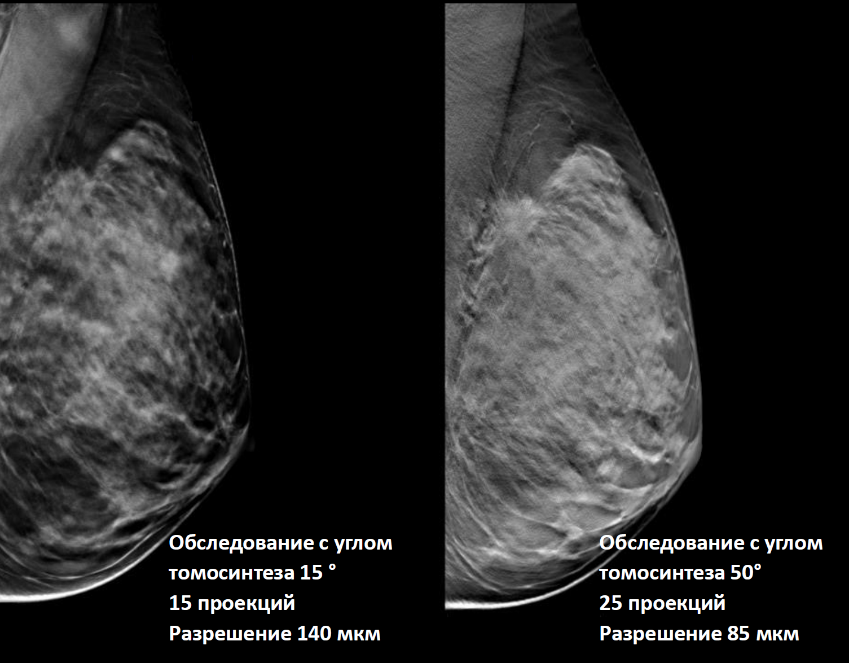

Факторы качества цифрового томосинтеза (DBT)

- Угол наклона рентгеновского излучателя. Больший угол даёт больше информации, т.к. уменьшается степень наслоения соседних объектов.

- Количество получаемых проекций. Чем больше количество проекций, тем меньше уровень артефактов.

- Толщина среза влияет на степень наслоения по вертикали соседних объектов.

- Размер пикселя активного элемента матрицы детектора всегда обратно пропорционален качеству визуализации.

Сравнение томосинтезных срезов, сделанных на разных маммографических аппаратах